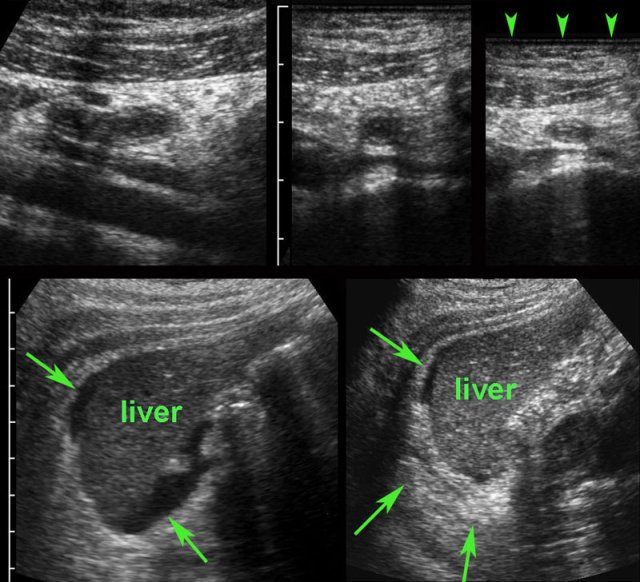

TOA case 2

Young

woman presenting with severe acute abdominal pain clinically suspect for perforated

appendicitis.

Lab-findings at admission: WBC 10.6 - CRP 6 Two days later: WBC 19.7 - CRP 459

US showed a large inhomogeneous masses left and

right of the uterus, suspect for tubo-ovarian abscess (TOA).

There

was also a paralytic ileus with secondary wall thickening of small bowel (b.) and

hyperechoic preperitoneal and mesenterial fat.

Puncture of a little ascites yielded

2 cc of yellow, turbid fluid.

CT

confirmed the US findings but additionally demonstrated a pyosalpinx (p.)

within the tubo-ovarian mass on the right side. Antibiotics are started intravenously.

Two

days later PCR of both cervical and urethral probes as well as the punctured

fluid were positive for Chlamydia.

Rapid recovery with only antibiotics.